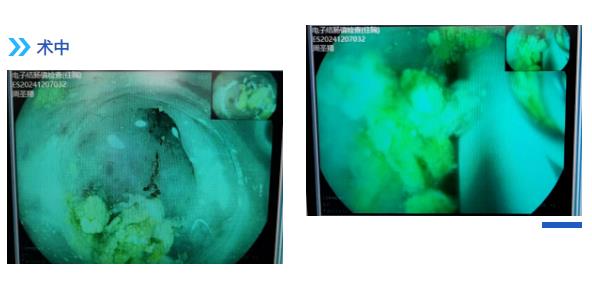

退镜观察见阑尾开口呈半月形,回盲瓣唇型、光滑,通过活检孔道送入一次性成像导管, 后寻腔将一次性成像导管送入阑尾腔,腔内可见多块成形粪石,使用一次性内镜取石网篮粉碎取出多块粪石,应用生理盐水冲洗阑尾开口可见粪石流出,同时可见絮状脓性分泌物流出,后反复观察阑尾腔内,无明显粪石存留,阑尾腔内管壁局灶略粗糙充血发红,近阑尾口处为著。余所见肠腔通畅,肠瓣形态正常,粘膜光滑,无充血水肿, 血管网清晰,未见糜烂、溃疡、息肉、瘢痕及新生物。